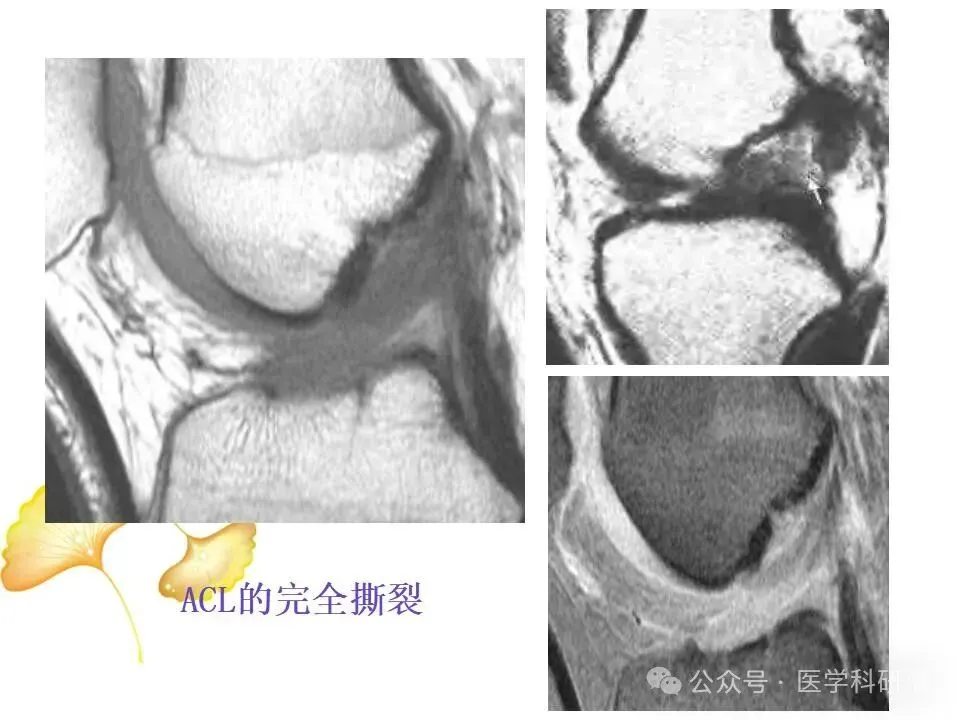

• 前交叉韧带(ACL):位于膝关节内部,负责防止胫骨向前滑动以及控制膝关节的旋转运动。

当膝关节遭受剧烈撞击或扭伤时,上述韧带可能发生拉伤、部分撕裂或完全撕裂,其中ACL损伤最为常见。韧带损伤会导致膝关节稳定性降低,影响日常活动和运动表现。

二、MRI在膝关节韧带损伤诊断中的应用详解

通过这些技术,医生能够准确判断韧带的损伤类型、程度和范围,从而制定出合适的治疗方案。